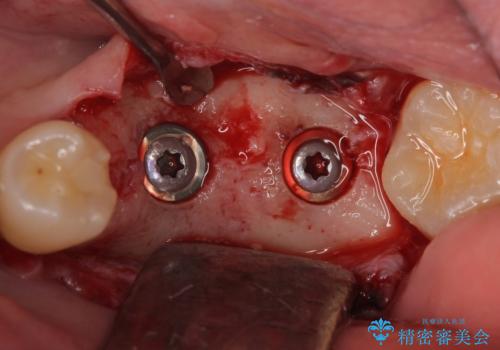

左下にインプラント(ストローマン)を2本埋入し、オールセラミッククラウンによる補綴を行いました。

当院では主にストローマンという種類のインプラントを治療に用いています。

ストローマンは世界的にもNo1のシェアを誇り、骨との適合にも優れたインプラントです。

カスタムアバットメントについて

カスタムアバットメントは患者様それぞれの歯茎に合わせて製作されたオーダーメイドのアバットメントです。

既製のアバットメントに比べ適合がよく、高い清掃性を誇ります。

- 外科手術のため、術後に痛みや腫れ、違和感を伴います